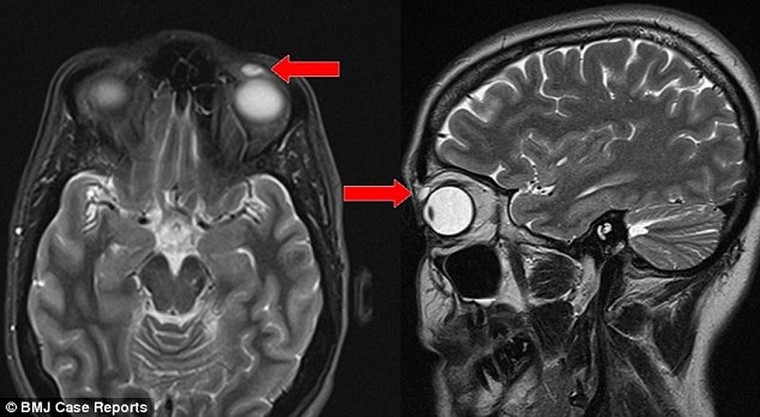

Bản chụp MRI cho thấy trên mí mắt bệnh nhân có một nốt nhỏ, kích thước 8mm x 4mm x 6mm, ban đầu bác sĩ cho rằng chỉ là mụn bọc. Tuy nhiên, khi lấy dị vật ra, các bác sĩ phẫu thuật vô cùng kinh ngạc khi phát hiện ra khối u này thực sự là một cái kính sát tròng đã rạn vỡ.

Trong lịch sử y khoa thế giới từng có 4 trường hợp kính sát tròng di chuyển do va chạm với vùng mắt. Nhưng đây là trường hợp mà kính sát tròng nằm trong mắt lâu nhất từng thấy, trong khi hầu như không hề có triệu chứng nào biểu hiện ra ngoài.